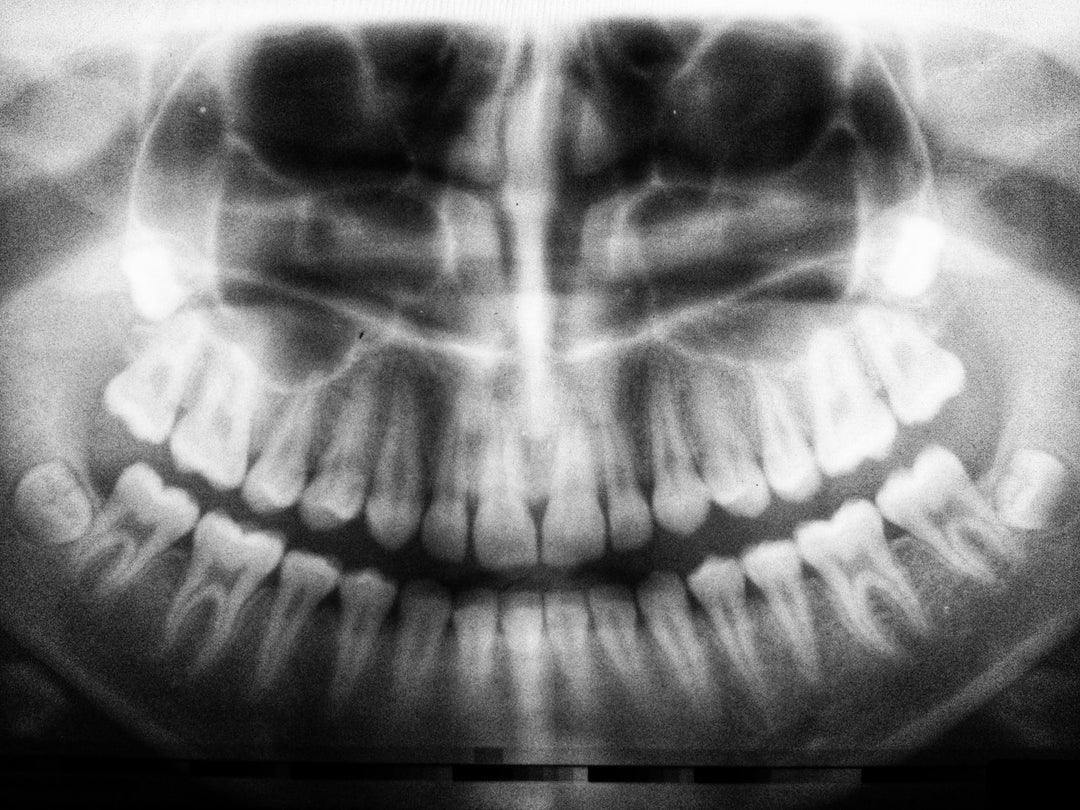

- Cracked, damaged, or blunted teeth

- Damaged fillings or crowns

- Permanent tooth damage

Dental Corrective Procedures

One dental procedure that may help with the reshaping or balancing of your bite is called reductive coronoplasty. This can be very effective for those whose uneven bite, crooked or crowded teeth are the cause of grinding.